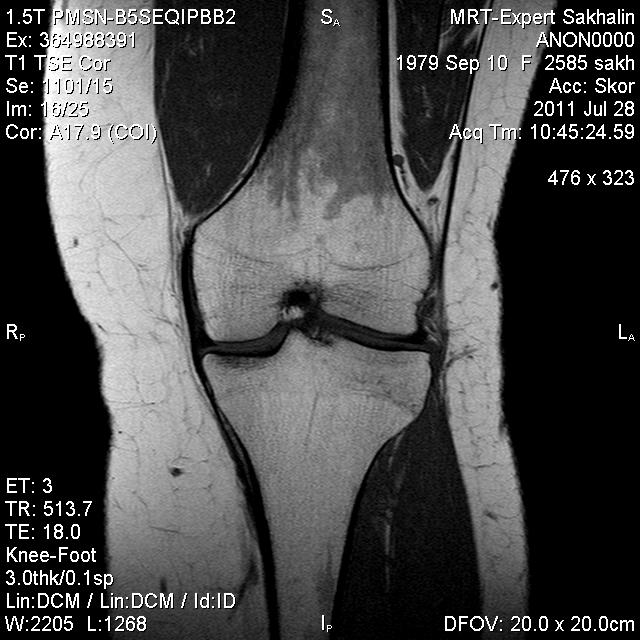

Коленный сустав

Подглядела случай у коллеги.

Что это может быть?

Не вижу криминала. А на что жалуется девушка?

P.S. В костях - это, скорее всего, резидуальный красный костный мозг.

Жалоба у всех одна на всех-болит.

участки гемопоэтического костного мозга